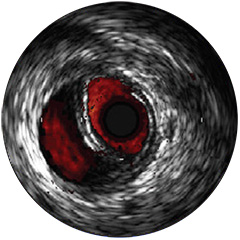

Figura 4